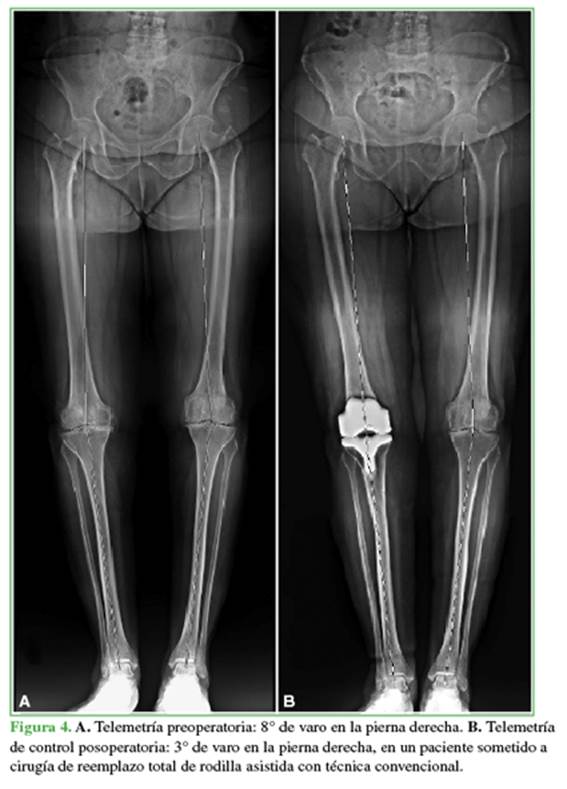

En este estudio, los RTR primarios guiados por sistema de navegación fueron más precisos para lograr la alineación final del miembro en un eje mecánico de 0° ± 3° (Figura 3) en comparación con el RTR mediante técnica convencional (Figura 4).

El 14% del grupo A tenía un IMC >35 kg/m2 y, en el grupo B, fue superior, pero la diferencia no fue significativa. En cuanto al eje del miembro obtenido por telemetría posoperatoria, expresado en grados, fue de 1° y 3° en la mayoría del grupo con prótesis navegada (70%) y de 0° en el 18%. En el grupo B, estos porcentajes fueron menores: 1-3° (46%), 0° (3%) y 6° o más (21%), con una diferencia estadísticamente significativa (Figuras 1 y 2). En lo que respecta a la desviación del eje en varo y en valgo, las cirugías con sistema de navegación arrojaron un resultado del 10% en valgo (L) y aquellas con técnica convencional, del 19%. El resto de los pacientes tenía un eje posoperatorio en varo (R).